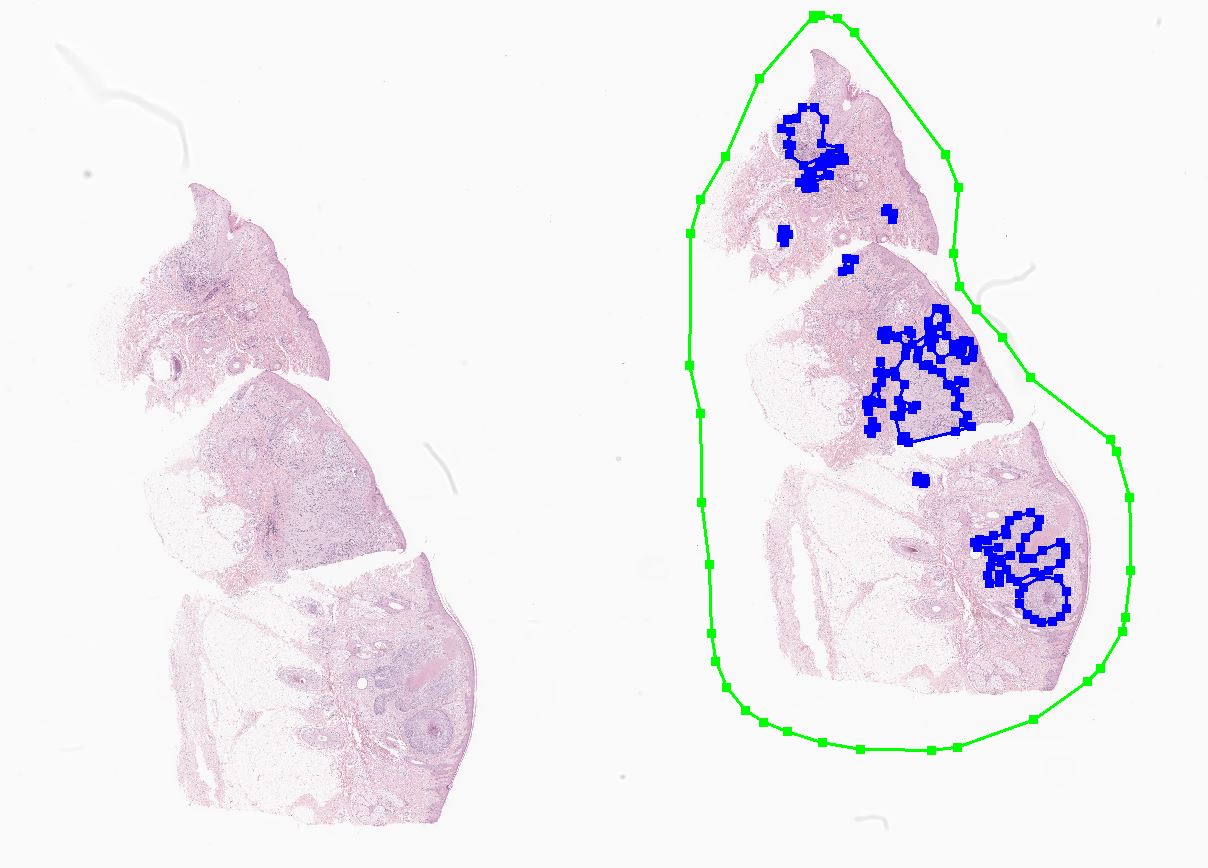

(2) 라벨링 데이터 실제 예시

![[ 라벨링 데이터 실제 예시 ]](/cms/images/ckimages/71519/annotation_schema_9.jpg)

[ 라벨링 데이터 실제 예시 ]